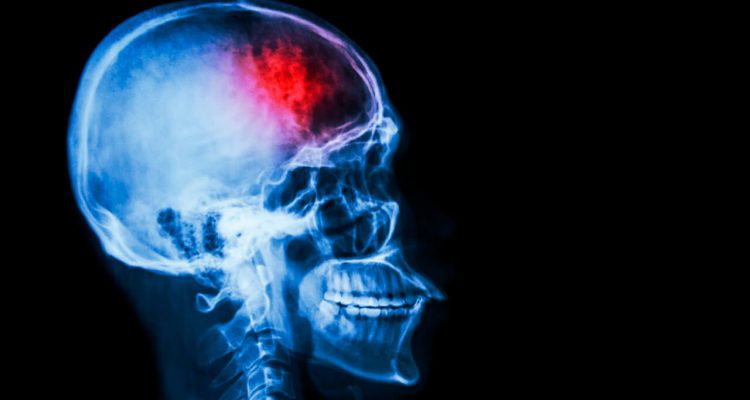

Інсульт-це гостре порушення кровопостачання головного мозку. Коли кров перестає переносити кисень до клітин, вони починають відмирати. Один з найпоширеніших видів інсульту – ішемічний. Однією з його причин може стати тромб, що відірвався: він перегороджує посудину і заважає кровотоку.